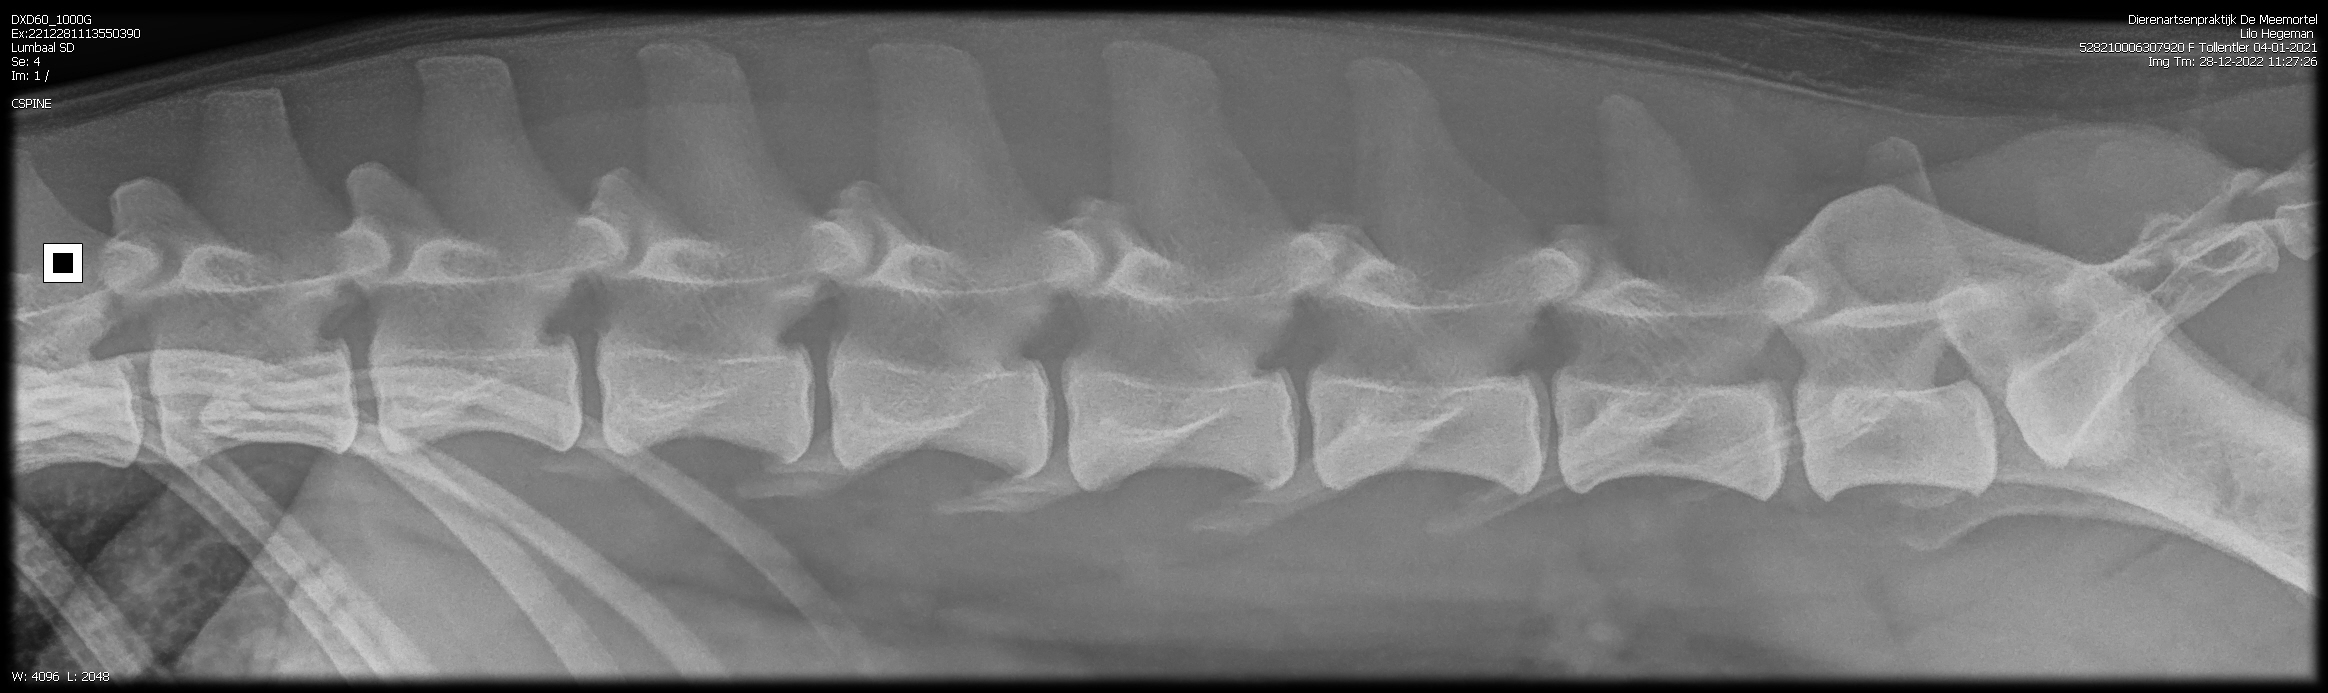

Lilo onze eerstgeborene Tollentler in de kleur Tan is inmiddels volledig getest.

De heupen perfect zoals je kunt zien.

HD-A

Zo ook het overige. Zie onderstaand.